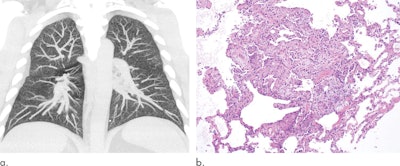

Finally, in the coming year, look for research that explores CT-specific findings that distinguish EVALI from COVID-19, according to Kligerman.

In January, he and a team of colleagues published a study indicating that x-ray followed by CT or CT pulmonary angiography best identifies key imaging patterns indicative of EVALI. The group is now preparing a manuscript that describes the incidence of certain patterns of acute and subacute lung injury with EVALI and explores whether certain imaging findings and patterns are associated with the type of substance vaped, as well as the frequency and duration of vaping.

"Even during the pandemic, recognizing the imaging patterns associated with EVALI is important," Kligerman told AuntMinnie.com. "While some patterns and imaging findings are nonspecific and can be seen with various causes of lung injury, including COVID-19, there are others that really should make one think of EVALI. This distinction can be quite important as treatments vary depending on the cause of lung injury."